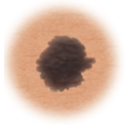

Moles (nevi)

Small skin marks caused by pigment-producing cells in the skin. Moles can be flat or raised, smooth or rough, and some contain hair. Most moles are dark brown or black, but some are skin-colored or yellowish. Moles can change over time and often respond to hormonal changes.

Most moles are benign and no treatment is needed. Some benign moles may develop into skin cancer (melanoma). See below for signs.

Atypical moles (dysplastic nevi)

Larger than normal moles (more than a half inch across), atypical moles are not always round. Atypical moles can be tan to dark brown, on a pink background. These types of moles may occur anywhere on the body.

Treatment may include removal of any atypical mole that changes in color, shape, or diameter. In addition, people with atypical moles should avoid sun exposure, since sunlight may accelerate changes in atypical moles. People with atypical moles should see a healthcare provider for any changes that may indicate skin cancer.

Certain moles are at higher risk of changing into malignant melanoma, a form of skin cancer. Large moles that are present at birth and atypical moles have a greater chance of becoming cancerous. Finding cancerous skin growths early is important because that’s when treatment is most likely to be effective. Removing the melanoma through surgery seems to work best as the treatment. When a melanoma is diagnosed early, surgery usually removes all the cancer.

Use this ABCDE chart below to help you see changes in your moles at the earliest stages. The warning signs include:

Asymmetry

When half of the mole does not match the other half

Border

When the borders (edges) of the mole are ragged or irregular

Color

When the color of the mole varies throughout

Diameter

If the mole's diameter is larger than a pencil's eraser

Evolving

Changes in the way the mole looks over time